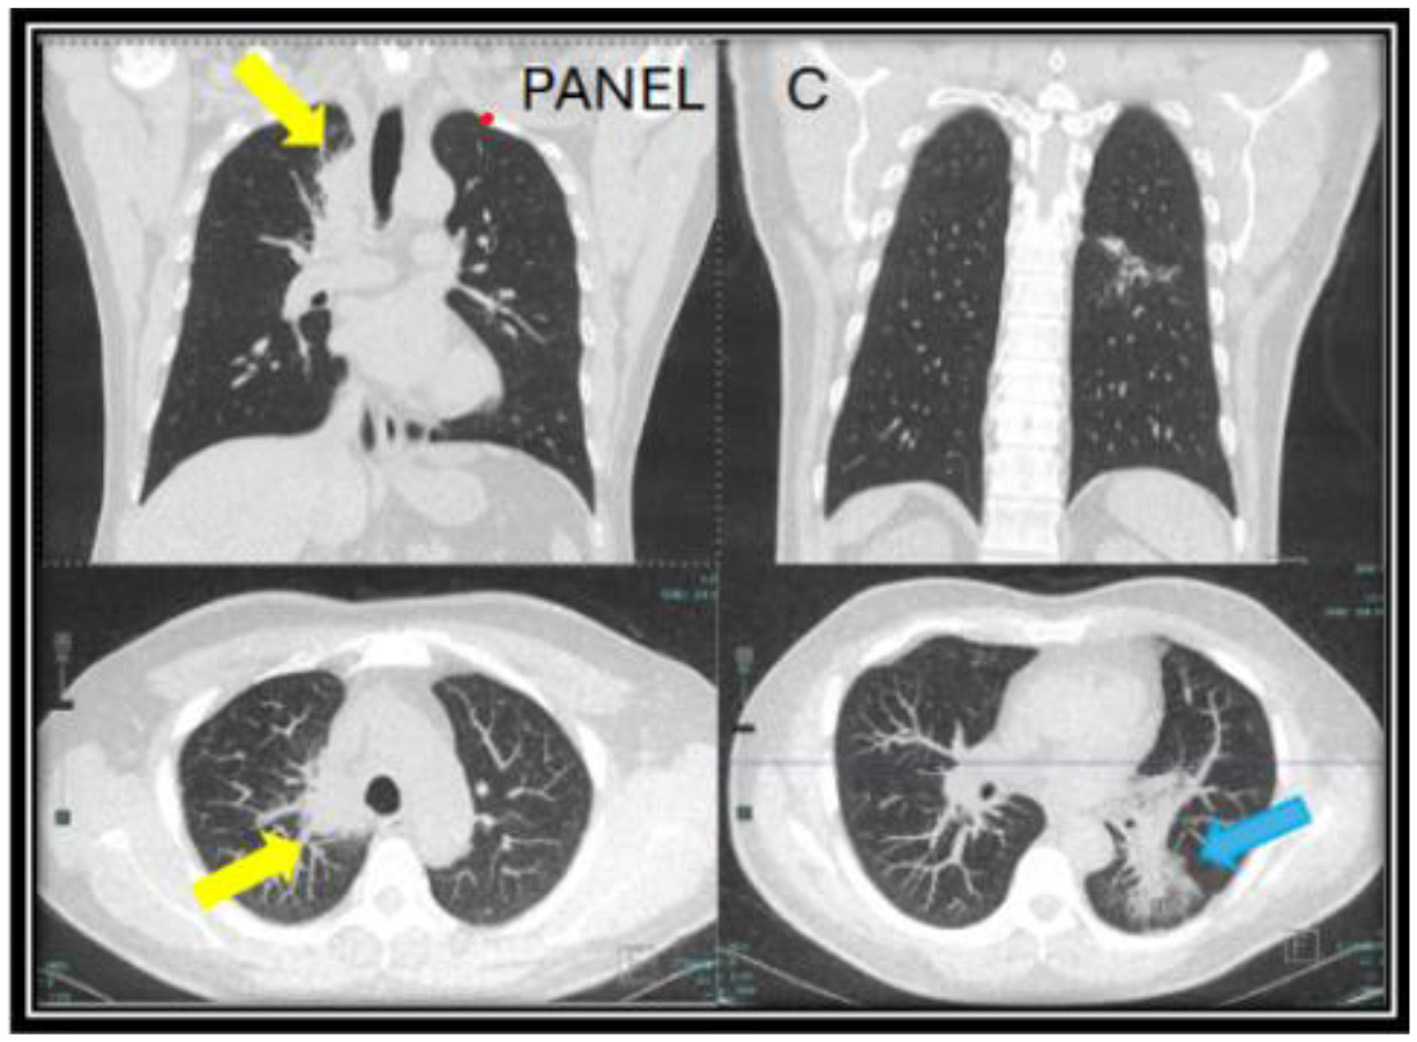

However, the patient expressed concerns about a new onset dry cough a year later. He was urged to present to the clinic for a clinical workup, but he did not follow up for 6 months. When he presented to the clinic, he continued to endorse persistent symptoms of dry cough and shortness of breath. A CT chest revealed a new right upper lobe infiltrate, and the patient's Coccidioides CF titer had spiked to 1:64 (Figure 2). Recognizing this as a relapse of pulmonary coccidioidomycosis, the patient was promptly restarted on itraconazole, which resulted in dramatic resolution of symptoms within 2 weeks. With initiation of itraconazole, the patient's ruxolitinib dose was again reduced to PO 5 mg BID. Follow-up testing showed a steady decline in CF titers to 1:4, confirming the effectiveness of continued antifungal therapy. Repeat CT imaging revealed resolution of right upper lobe infiltrate after 2 years of itraconazole use (Figure 3). At the time of publication of this paper, the patient has continued to maintain effective disease control on itraconazole and ruxolitinib and will continue with indefinite antifungal treatment.

Figure 2. CT chest images taken a year after of being off of itraconazole (year two) when the patient developed a new persistent cough associated with a rise in Coccidioides complement fixation titers. A new mass-like consolidation of the medial right lung apex measuring 5.1 × 2.9 × 0.8 cm (yellow arrow) was noted. The superior segment of the left lower lobe continued to improve (blue arrow). The nodular consolidation has decreased, and mild scarring and bronchiectasis now persisted in this area (C).

Figure 3. A follow up CT chest done at year four while being on long-term itraconazole showed resolution of the right upper lung infiltrate (yellow arrows) and residual reticulated bronchiectasis in the left lower lobe [blue arrow in (D)].